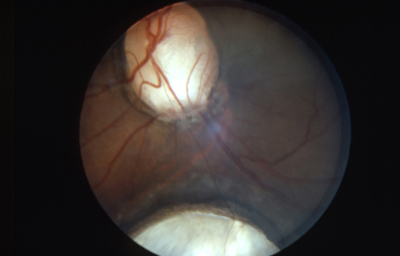

Colobomas

Desde el comienzo del estudio de la embriología del ojo, se ha hecho relación entre el cierre de la Fisura de la Copa Óptica y los Colobomas Oculares.

Se los clasifica como “Típicos” aquellos colobomas infero-nasales, y en general afectan Iris, Cuerpo Ciliar y Coroides. “Atípicos”aquellos situados en cualquier otro lugar del Iris.

Dibujo de vaso persistente produciendo muesca en el borde de la copa

Foto tomada de: Ida Mann; The development of the Human Eye. 1969. Grune & Straton Inc N.Y

Dibujo de vaso persistente produciendo muesca en el borde de la copa

Embrión humano de 2 meses

Colobomas típicos con diferentes grados de defecto en el desarrollo

Colobomas Atípicos.

Archivo Fotográfico Dr. Francisco Barraquer

Archivo Fotográfico Dr. Francisco Barraquer

Las posibles explicaciones de su origen siguen en discusión y la pregunta es: ¿la causa primaria de los colobomas es Ectodémica o Mesodérmica? Podría tratarse de una falla localizada en una porción del margen ectodérmico de la copa óptica o bien, a una persistencia indebida del mesodermo fetal, que secundariamente inhibiría el crecimiento del ectodermo en contacto con él.

Existen múltiples argumentos relacionados, pero ninguno definitivo. actualmente se habla más de los errores genéticos que pueden producir estos defectos.